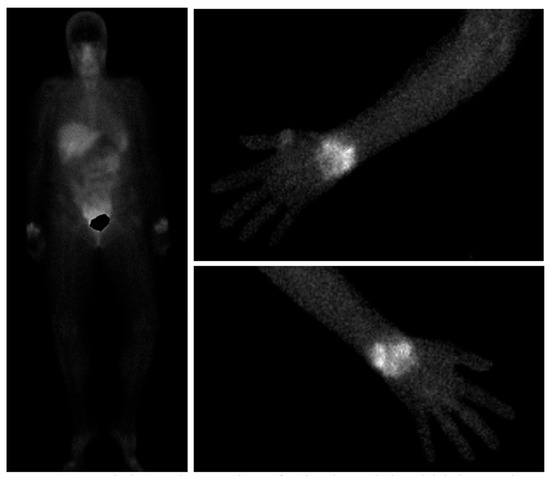

Despite important advancements in arthritis research, significant challenges remain, particularly in the early diagnosis of these conditions and the development of personalized treatments tailored to individual patients. This Special Issue aims to address these issues by focusing on innovative diagnostic methods, such as advanced imaging techniques, and a deeper understanding of disease mechanisms. It will also explore cutting-edge treatments, including disease-modifying anti-rheumatic drugs (DMARDs), biologics, and targeted therapies.

A key goal of this Special Issue is to improve how healthcare professionals differentiate between similar types of arthritis, enabling quicker and more accurate diagnoses, and to better assess the extra-articular manifestations of these diseases.